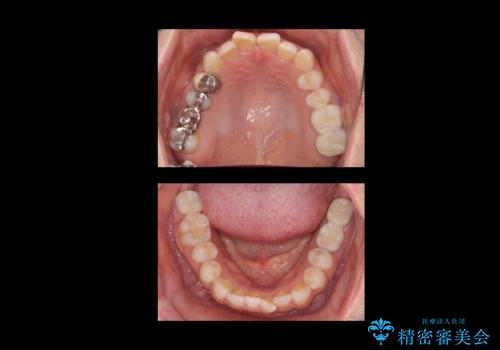

合計3本の奥歯を抜歯したところに、インプラント治療を行っています。

また、左上奥歯の根の治療および右下の虫歯治療も併せて行っています。